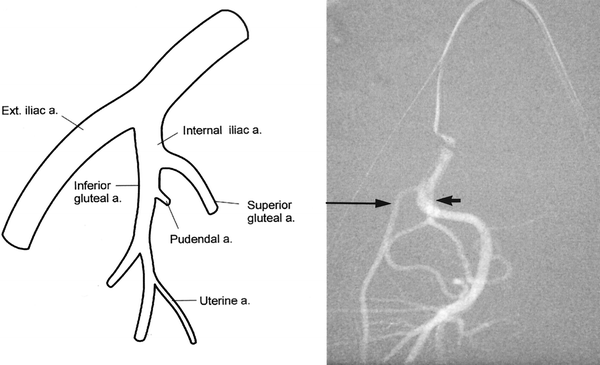

• Figure 4 From Uterine Artery Emerging Variants

• Selective Catheterization Of The Right Uterine Artery With

• Uterine Artery Angiography Demonstrating Fibroids